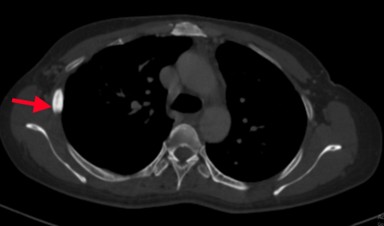

 Chụp cắt lớp vi tính ổ bụng:

Hình 12: Hình  ảnh CT ổ bụng sau 6 tháng điều trị: Khối nhu mô gan hạ phân thùy S7 giảm tỷ trọng, ngấm thuốc kém sau tiêm,

Kích thước tổn thương giảm dần qua  các đợt   điều  trị: và 15mm (mũi tên xanh).